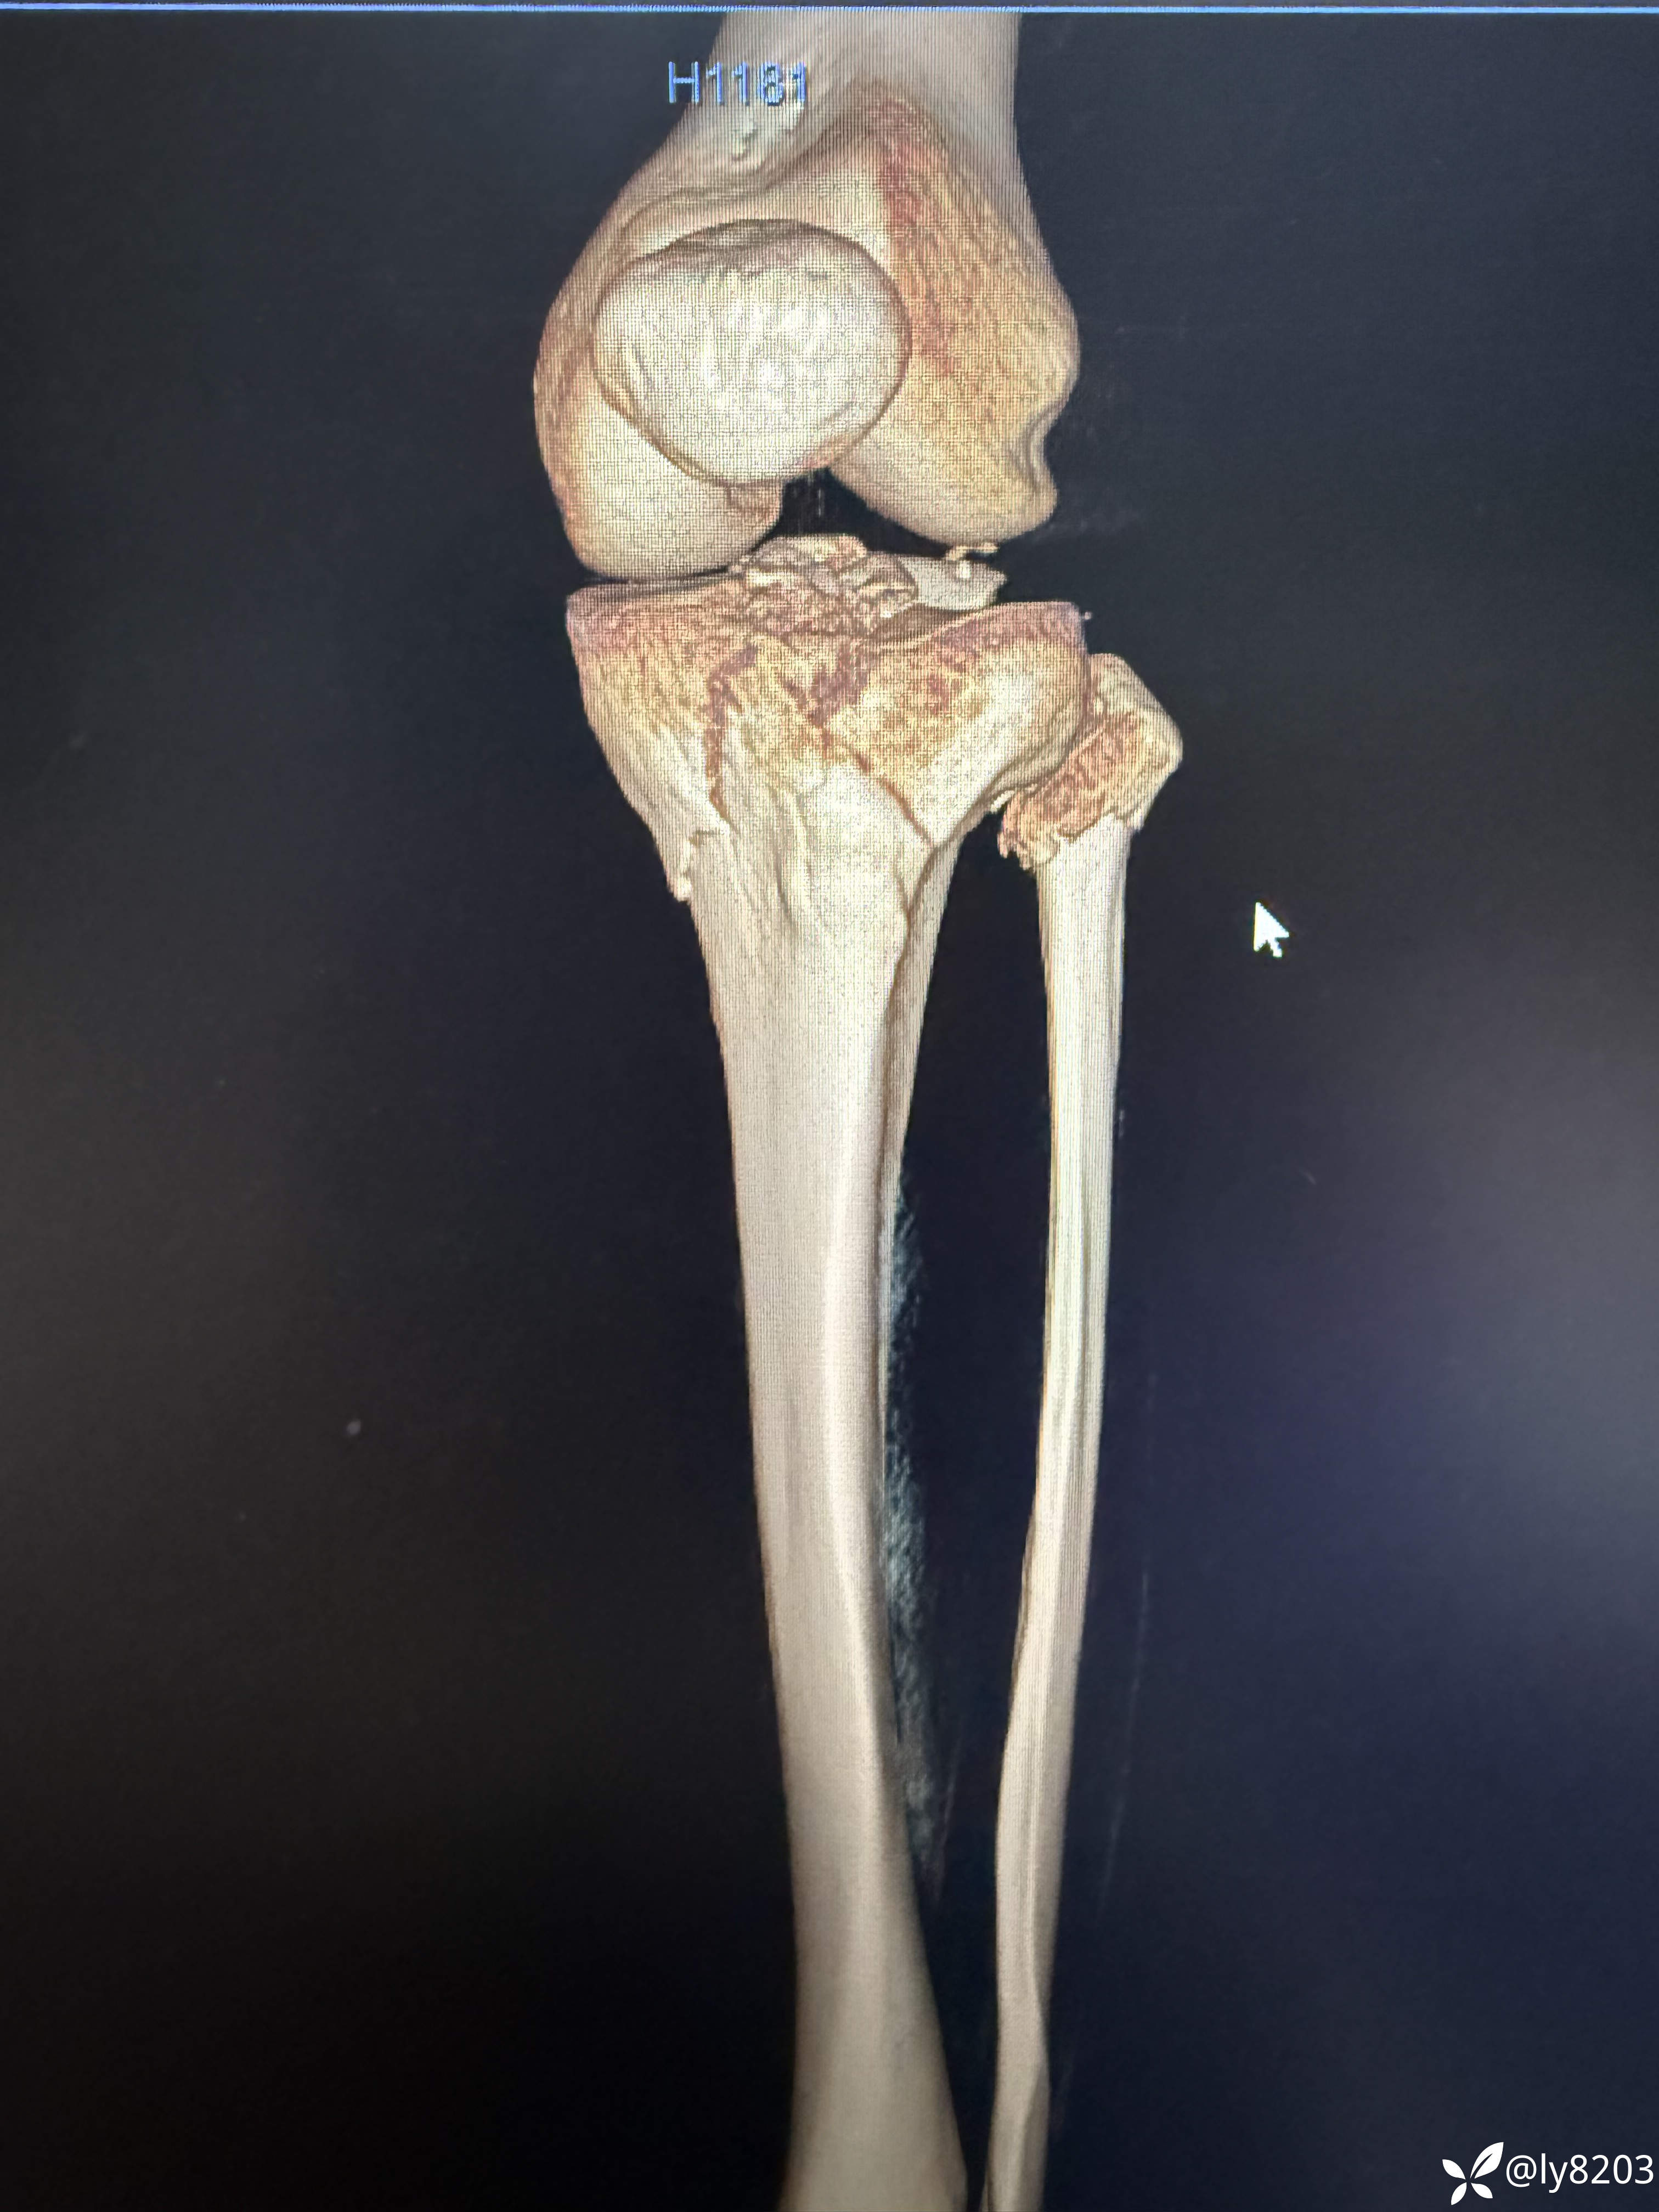

这个难点在后外侧游离骨块。按胡老师的方法,先将外侧平台用两个弯钳抬起,与前髁间棘对齐后克氏针固定,再从外侧副韧带后缘用骨拨托住并往前顶,从关节线用弯钳从前面抬,没成功,随即改变方案,用胡式顶棒外侧经皮顶,后侧骨块解剖复位,后缘与外侧平台丝滑对齐,克氏针固定。剩下就是常规操作了。以往都是大切口,截骨处理后外侧,胡教授的方法避免了切口大,创伤大。有利于加速康复。